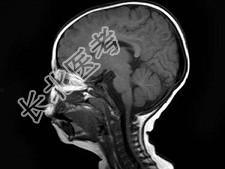

- 单项选择题男,1岁, 癫痫发作3次,智力反应低下, 头颅MRI扫描如图,最可能的诊断为 ( )

D、结节性硬化